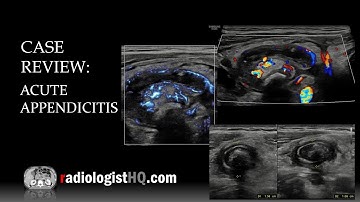

Ultrasound video showing inflamed gangrenous appendix, intramural gas shadows in base of appendix